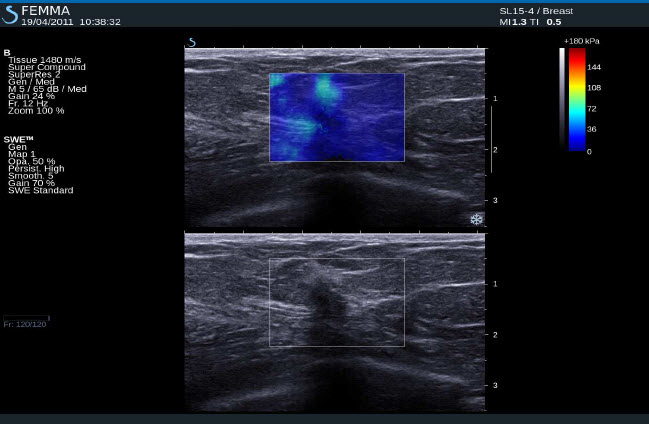

Normální tkáň prsu

Cysty

Fibroadenom